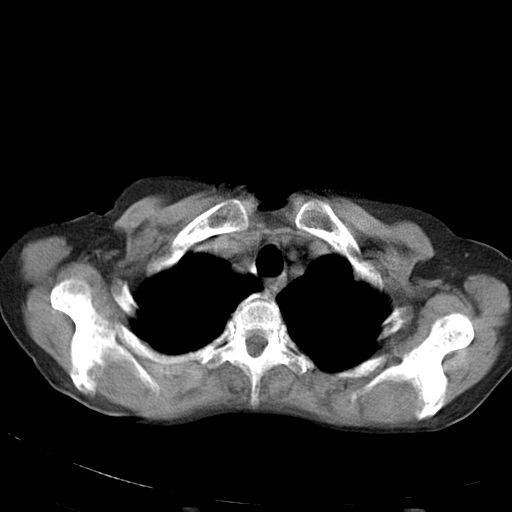

以下是引用dyqct在2006-12-7 21:08:00的发言:[br]考虑:1、肝内外胆管多发性结石伴肝左叶外侧段肝萎缩;[br] 2、右膈下多发脓肿;[br] 3、右侧少量胸腔积液、斜裂积液;[br] 4、左肾囊肿。

以下是引用jiazh在2006-12-7 20:37:00的发言:[br]肝脏周围半狐形低密度影,肝脏表面受压推移,考虑膈下脓肿可能性大;2、右侧胸腔积液

以下是引用拾荒者在2006-12-7 21:44:00的发言:[br]肝内外胆管多发结石,右膈下多发脓肿,右胸膜腔及叶间裂积液,左肾囊肿。[br] [br]